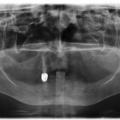

Установка 10 имплантантов на беззубую челюсть с помощью компьютерной программы: Через месяц после удаления

Через месяц после удаления